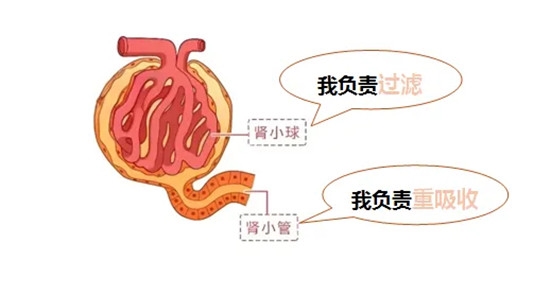

肾小球和肾小管

是肾脏最基本的功能单位,

参与了尿液形成的主要过程。

负责过滤功能的是肾小球,它就像一个具有特定孔径的筛子,血细胞和大分子蛋白质不能通过这个筛子而被留在血液中,一部分水、无机盐、葡萄糖、尿素等这些小分子物质能够自由通过筛子而被过滤到肾小囊腔中形成原尿。

蛋白质作为人体必需的营养物质,通过肾小球的“筛选”和肾小管的“回收”,几乎全部回到血液中循环利用,所以正常情况下尿液中是几乎不含蛋白的。

但是,在肾脏发生疾病时,如果肾小球这个筛子的孔径变大,原本不能通过筛子的蛋白质就会漏出到原尿中,而肾小管又不具备回收这种大分子蛋白的能力,从而导致蛋白在尿液中出现。

所以尿液中出现大分子蛋白的时候,首先考虑肾小球病变。